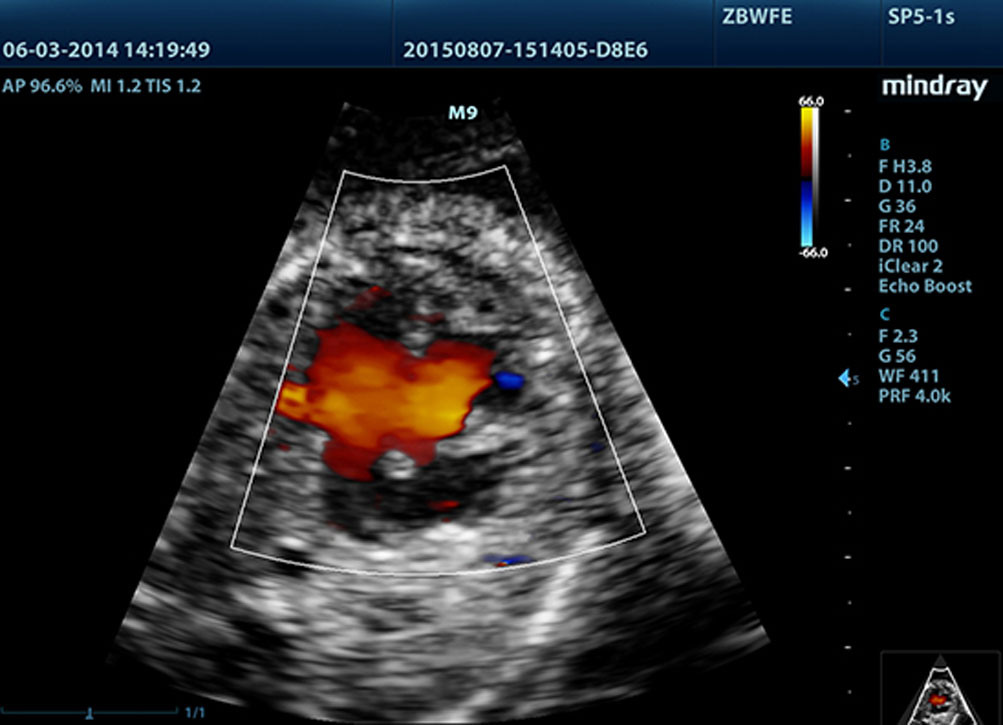

LVO dengan Stress Echocardiography

Kemampuan premium M9 memungkinkan opasifikasi LV pada saat terjadi tekanan. Fitur tersebut memaksimalkan perbedaan antara jaringan miokardial dan blood pool, sehingga permukaan endokardial terlihat lebih jelas. Fitur Stress Echo pada M9 mencakup paket lengkap untuk ekokardiologi beban farmakologis dan beban latihan. Paket ini didukung sistem laporan fleksibel yang dapat dioptimalkan sesuai dengan setiap kebutuhan.